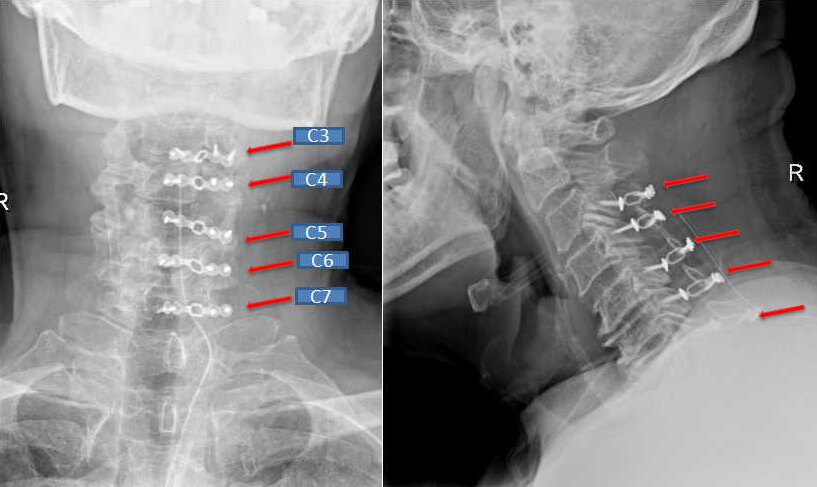

小杨术后X线,内固定位置良好

老谢术后X线,内固定位置良好